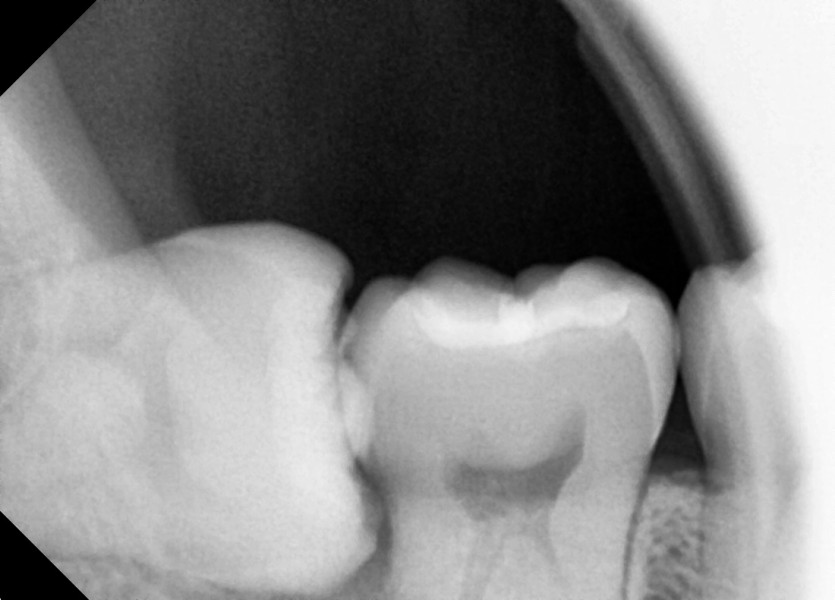

#38,48 사랑니 발치

구강 외과 전문의가 당일 발치했습니다.